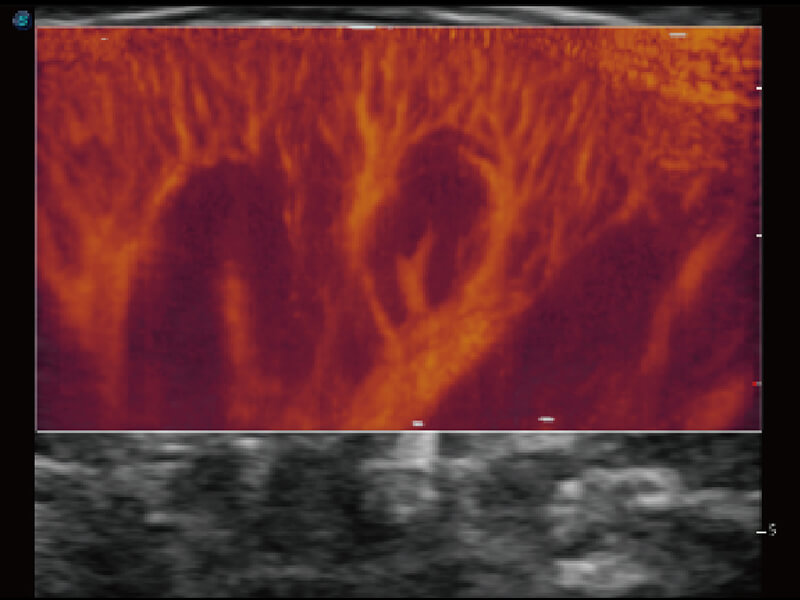

性能优异的硬件架构,极大提升超声系统的运行效率和数据处理能力。相比以往超声成像系统,Wis+平台为您带来极快的响应速度和成像帧频,提升检查流畅度。